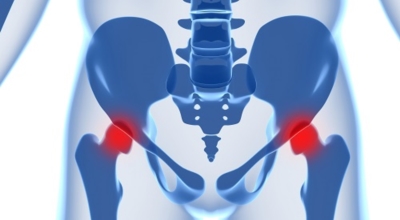

3. 고관절 통증 증상 - 엉덩이 통증

이 경우는 허리디스크나 척추협착등의 척추질환이 동반되어 생기는 고관절 통증입니다. 이와 같은 경우도 장기간 서있는 자세가 힘들어 지고 걸음걸이가 불편해 져요. 또한 척추의 신경이 눌리면서 허벅지 또는 종아리 통증을 동반하고 골반 부위에 통증을 유발합니다. 원인으로는 장시간 앉아있거나 허리에 안좋은 자세를 유지할 경우에는 통풍 또는 류머티스와 같은 질병으로 인해 발생 할 수 있어요.

고관절 통증을 방치한다면 뼈가 점차 약해져 골다공증이 발생할 수 있다고 하며, 고혈압이나 당뇨 과 같은 다른 질병으로 이어질 가능성이 있다고 해요. 그리고 고관절 통증이 심해져 보행하는데 어려움을 겪을 경우, 점차 허리 질환으로까지 이어져 허리 통증을 겪을 수도 있답니다.